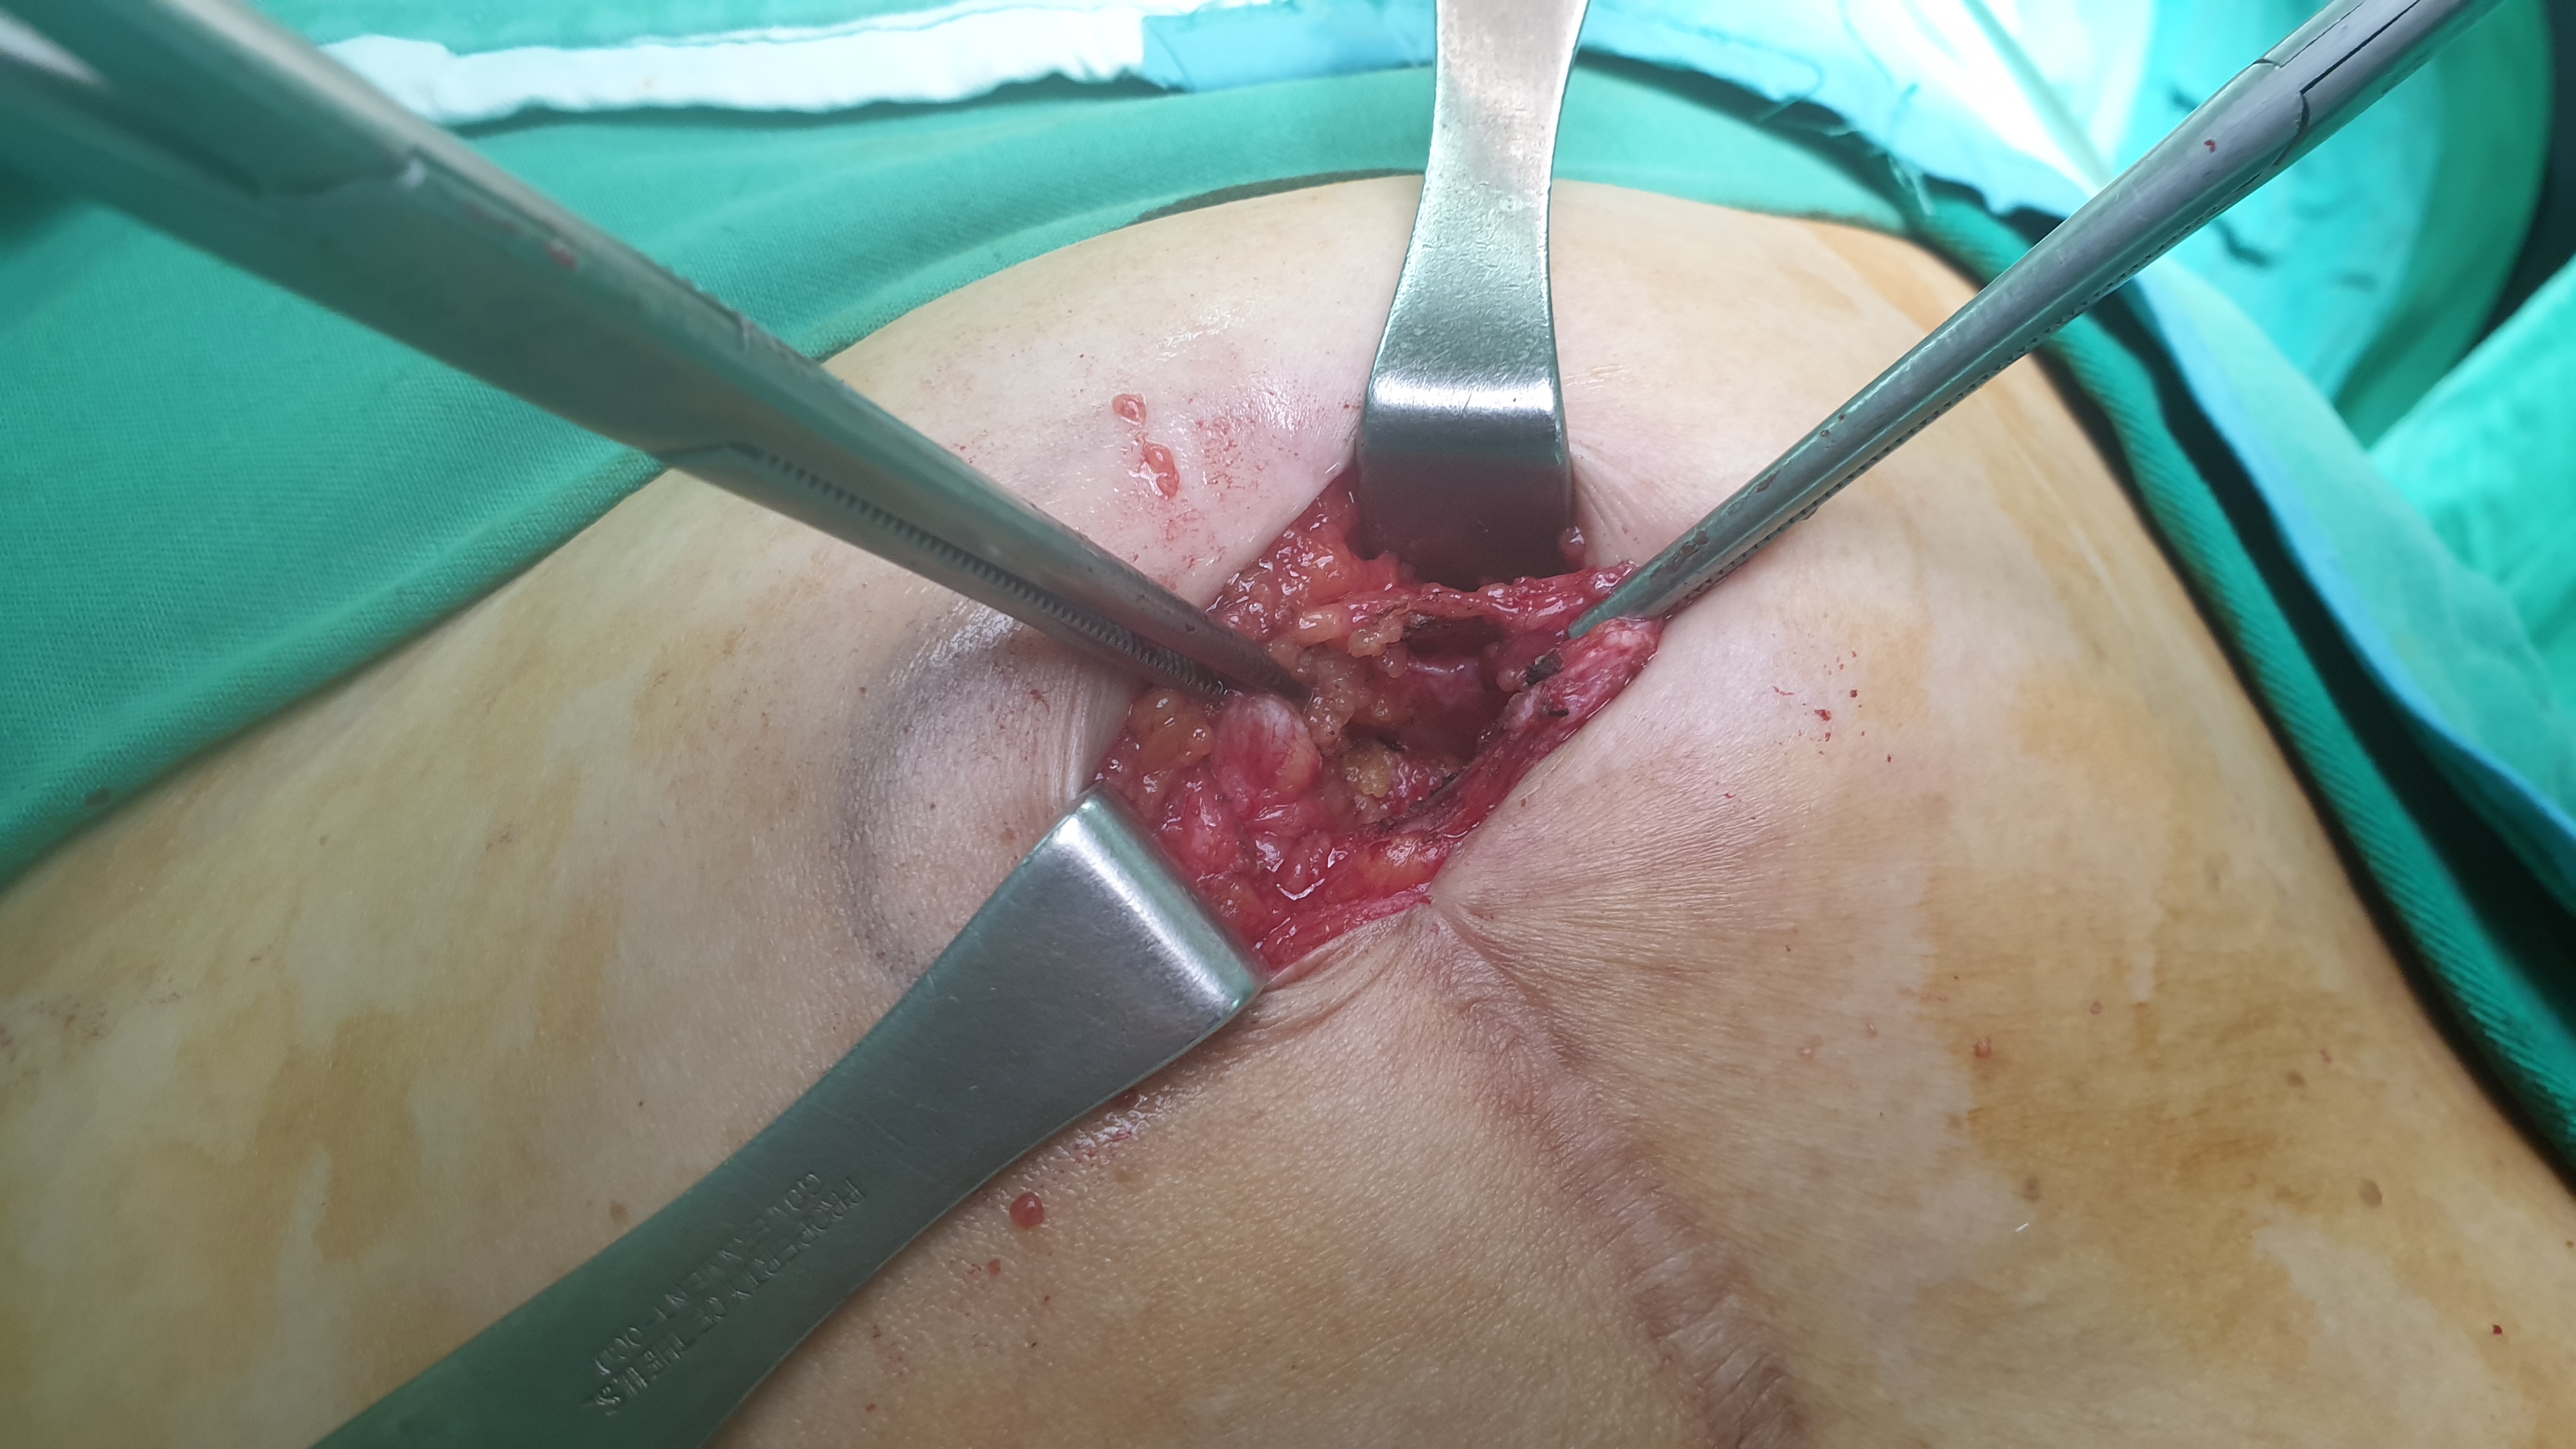

탈장된 부위 바로 위의 피부를 절개하여 탈장된 장간막을 복강내로 집어 넣고 나면 위 그림과 같이 근막의 결손으로 인해 구멍이 뻥 뚫린 것이 확인됩니다.

절개 부위가 크지 않아 인공막 삽입은 필요 없습니다. 탈장 봉합술을 바로 시행합니다.